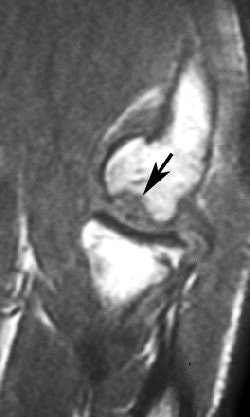

![]() |

| An 18-year-old man with lateral elbow pain for four months and surgically proven unstable osteochondritis dissecans of capitellum. Anteroposterior radiograph of elbow shows osteochondritis dissecans lesion (arrow) as focal well-defined area of subchondral radiolucency. Kijowski R and De Smet AA, "MRI Findings of Osteochondritis Dissecans of the Capitellum with Surgical Correlation" (AJR 2005; 185:1453-1459). |